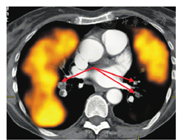

3.肺V/Q SPECT和CTPA联合显像。结构和功能联合显像的另一选择是将肺灌注SPECT显像与诊断性CTPA融合,这可在同一融合显像仪器上完成或在另一CT扫描后通过软件完成(图6)[58]。尽管这种方法需要合适的软件和专业操作者,但其对特定患者有价值,且利用CTPA能更好地引导放射科报告医师,观察到可疑的栓塞部位[59]。